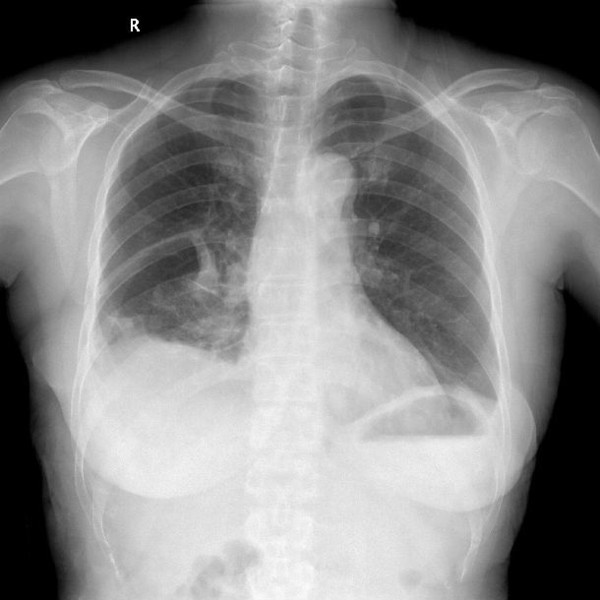

肺大泡(pulmonary bulla)(也作肺大疱)是指由于各种原因导致肺泡腔内压力升高,肺泡壁破裂,互相融合,在肺组织形成的含气囊腔。目前绝大多数的肺大泡手术均可在电视胸腔镜(VATS)下完成,2/3的患者术后症状明显改善。肺大泡一般继发于小支气管的炎性病变,如肺炎、肺结核或肺气肿,也有一些病因不清的特发性肺大泡。小支气管发生炎性病变后出现水肿、狭窄,管腔部分阻塞,产生活瓣作用,使空气能进入肺泡而不易排出,致肺泡腔内压力升高;同时炎症使肺组织损坏,肺泡壁及间隔逐渐因泡内压力升高而破裂,肺泡互相融合形成大的含气囊腔。产品参数